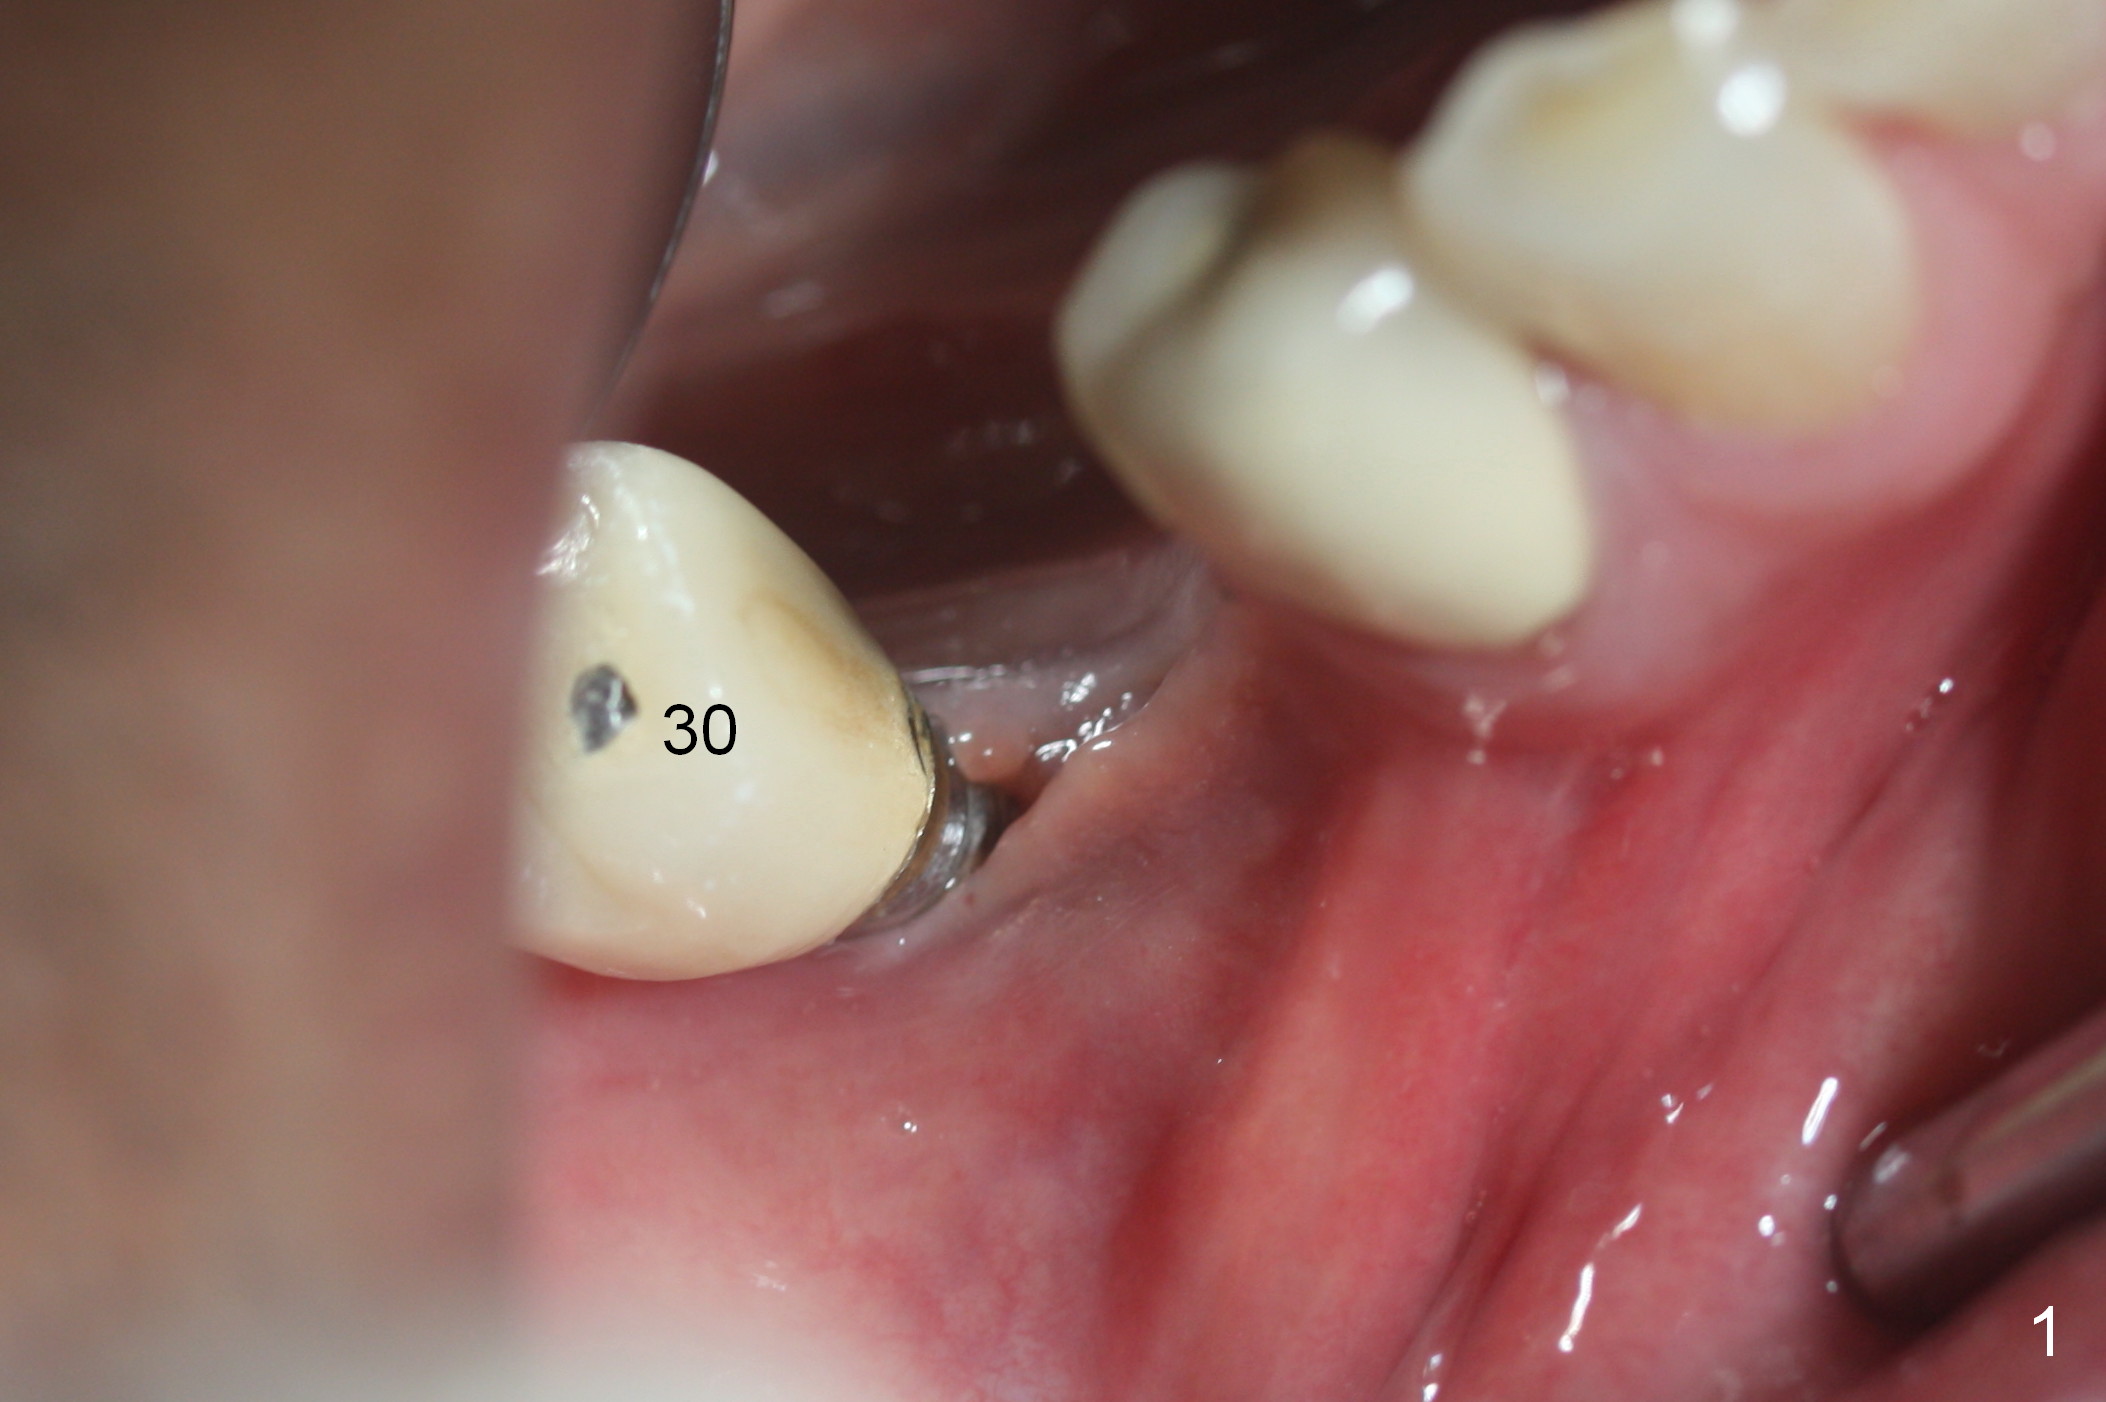

A 71-year-old man loses the implant at #29 five years post placement (Fig.1; 3 years post panoramic X-ray). The attached gingiva is nonexistent at #29 and 30. Gingival graft is necessary. The implant at #29 is placed as mesial (Fig.2) and lingual (Fig.5) as possible. If the implant at #30 is salvageable, place bone graft around the exposed implant threads (Fig.4,5 white circles). Cut a piece of 6-month collagen membrane, use a 4 mm tissue punch to punch 2 holes in the membrane (Fig.6 red circles) and cut open the hole for #30 lingually. Cover the membrane over the graft (Fig.5 red line), followed by PRF membranes (draw 5-6 tubes of blood).

Since the buccal plate is lower at #30 (Fig.7), place a new implant as lingual as possible if the existing one is deemed nonsalvageable. To distribute occlusal load and increase longevity of the implants at #29 and 30, an implant should be placed at the same time or later (Fig.2,8). Approximately 1.5 years later (after #19 implant), the patient returns with intention to restore missing teeth #29-31. The implant at #30 has been lost. CT will be taken for guided surgery. Also take photos to show whether there is lack of the keratinized gingiva at the ridge, as it is related to guided surgery. If the tough gingiva is missing, incision instead of tissue punch should be done prior to osteotomy.